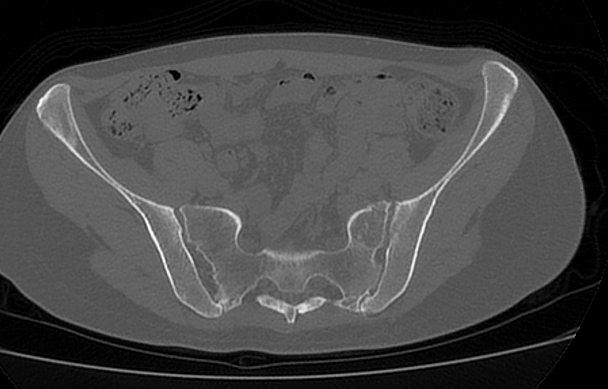

Для диагностики патологии костей таза применяются рентгенологические методы исследования, так как кости хорошо поглощают рентгеновские лучи и поэтому ярко видны на снимках. Современным наиболее информативным способом оценки состояния костных структур таза является мультиспиральная компьютерная томография. По сравнению с обычным рентгеном, когда изображения костей на снимках получается только в одной плоскости и накладывается друг на друга, мультиспиральная КТ позволяет получать послойные изображения в различных плоскостях. Томограф производит множество тончайших срезов исследуемой зоны толщиной от 0,5 мм, которые затем трансформируются при помощи компьютерной обработки данных в трехмерные пространственные модели.

Методика мультиспиральной КТ используется для диагностики переломов костей таза, когда обычный рентген недостаточно информативен. На снимках и трехмерных изображениях хорошо видны фрагменты костных отломков и взаимное расположение костей таза. КТ также назначается перед операцией и после хирургического вмешательства для оценки успешности проведенной операции и для контроля процессов регенерации костной ткани.